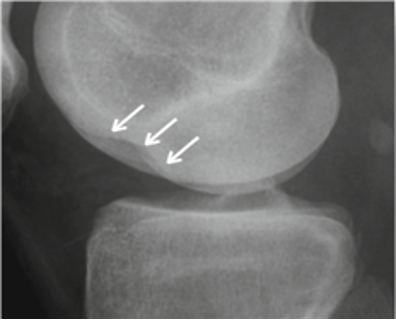

Bone lesions should also be investigated, especially notches in the lateral condyle (Figure 9) and fractures of the posterolateral tibial plateau (Figure 10). Cartilage damage, which may have negative consequences for the future of the knee, can also be found.

Studies have assessed long-term follow-up of knees with chronic anterior laxity. Nebelung et al. reported on the long-term follow-up of 19 athletes who were treated functionally in the 1960s. At 20 years of follow-up, 95% had undergone a meniscectomy and at 35 years, 65% required a total knee arthroplasty (54) (Figure 13). Neyret et al. compared the outcomes of isolated meniscectomies on stable versus unstable knees over 20–34 years. While 86% of patients with unstable knees had radiological OA, 38% of whom required repeat surgery at 30 years, 50% of patients with stable knees had radiological OA, only 5% of whom required repeat surgery (55).